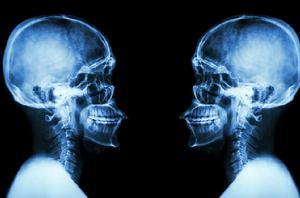

X射線

X線實質是一種電磁波,它具有電磁波的共同屬性。此外具有物理學、化學、生物學等方面的特有性質。 一.物理特性:

1、X線在均勻的、各項同性的介質中,是直線傳播的不可見電磁波。 2、X線不帶電,故而不受外界磁場或電場的影響。

3、穿透作用:X線波長短具有較高能量,物質對它吸收弱,因此具有很強的穿透本領。

X線檢查

醫用診斷X線機醫學上常用x線檢查作為輔助檢查方法之一。臨床上常用的x線檢查方法有透視和攝片兩種。

透視較經濟、方便,並可隨意變動受檢部位作多方面的觀察,但不能留下客觀的記錄,也不易分辨細節。

攝片能使受檢部位結構清晰地顯示於x線片上,並可作為客觀記錄長期保存,以便在需要時隨時加以研究或在複查時作比較。必要時還可作x線特殊檢查,如斷層攝影、記波攝影以及造影檢查等。選擇何種x線檢查方法,必須根據受檢查的具體情況,從解決疾病(尤其是骨科疾病)的要求和臨床需要而定。x線檢查僅是臨床輔助診斷方法之一。

正常值X線診斷上使用的X線波長為0.08-0.31埃(1埃=0.1納米=10的-10次方米)。